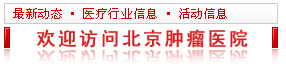

犹他大学研究者在KRAS突变最常见的胰导管腺癌中进行了研究,发现除了几乎全携带KRAS突变,胰导管腺癌中还普遍存在自噬增加,且对肿瘤的生长至关重要。跟KRAS很像的是,靶向自噬的治疗,也没有很好的效果。或许自噬和KRAS突变间存在着某种联系?

研究者发现,使用MEK抑制剂曲美替尼,或抑制ERK,抑或直接抑制RAS,都能让胰腺癌细胞中的自噬进一步增加。考虑到自噬对于细胞稳态的维持作用,或许这就是靶向RAS信号通路的疗效不佳的原因。

既然癌细胞可能靠自噬来抵御靶向治疗,那再把自噬抑制住不就行了吗?研究者将曲美替尼和自噬抑制剂氯喹联合使用,发现确实明显抑制了癌细胞的生长。向癌细胞中转入自噬抑制基因,也同样让它变得对曲美替尼敏感。提示正是自噬在靶向治疗中保护了癌细胞。

北卡罗莱纳大学的研究中,研究者进一步分析了抑制RAS通路如何增加癌细胞自噬。研究发现,抑制RAS下游的ERK,引起AMPK信号的激活和mTORC1信号的抑制。而这两种信号变化,都会导致自噬的增加。抑制ERK还会抑制细胞的糖酵解,从而让癌细胞更依赖自噬供能。此外,ERK的抑制还可能通过影响核苷酸的代谢促进自噬。